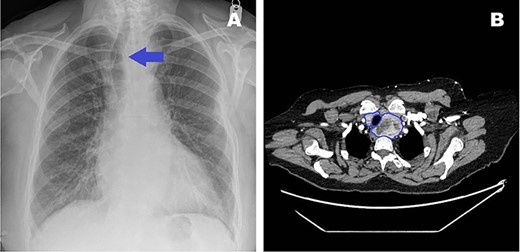

(A) CT thorax showing the extension of the retrosternal goitre (blue outline), causing tracheal deviation with extension and abutting the distal ascending aorta and arch. (B) 3D-reconstructed CT thorax lateral view highlighting goitre (blue outline) relationship with respect to ascending aorta and arch, and other mediastinal structures. (C) 3D-reconstructed CT thorax allowed planning of mini-sternotomy in relation to goitre position.

The goitre’s position would invariably make aortic cannulation and cross-clamping to perform the AVR difficult. It was deemed that the goitre needed removal first. However, the retrosternal position meant that normal cervical excision would be challenging and risky. Furthermore, due to the severe nature of the AS, she was considered unsafe to undergo thyroidectomy as a primary procedure. Endocrine surgeons were consulted and consensus dictated that combined procedure would be the best approach utilizing a mini-J sternotomy to aid in excision of the hemi-goitre prior to completing the AVR. 3D imaging was reconstructed to determine the anatomical relations in detail and plan the combined surgical approach meticulously (Fig. 2B and C).